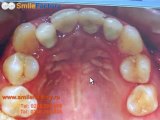

A cincea parte a tratametului ortodontic.

Ortodontia este disciplina stomatologiei, care se ocupa de alinierea dintilor si asezarea in pozitie corecta a maxilarelor. Niste dinti aliniati nu sunt doar o chestiune de estetica, ci si de sanatate dentara. Dintii inghesuiti sau aliniati gresit sunt mai greu de curatat si predispusi astfel diverselor afectiuni dentare si gingivale.